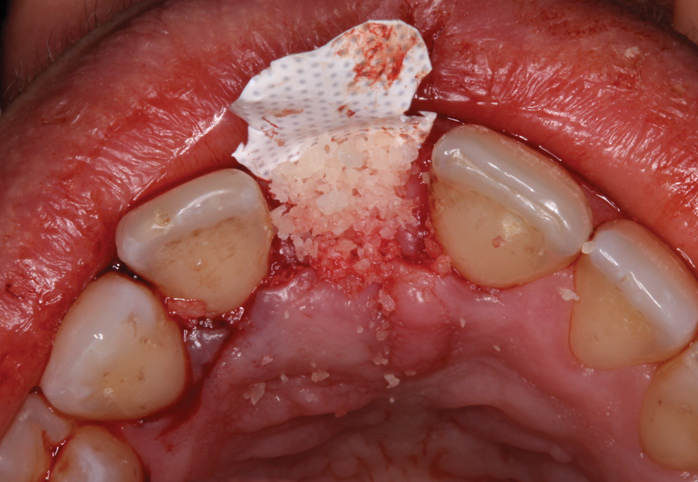

The right central incisor was removed atraumatically (Figure 3) without elevating a buccal flap. The presence of the buccal bone dehiscence was confirmed with the use of a periodontal probe. Measurements from the free gingival margin to the crest of the buccal bone and a horizontal assessment of the defect size indicated a dehiscence that was 8-mm tall and 5-mm wide. The distance from the free gingival margin to the most apical point in the socket was 10 mm.

A d-PTFE (Cytoplast) barrier was trimmed into the shape of an ice cream cone to conform to the socket's morphology (Figure 4). The barrier was placed inside the alveolus and compressed laterally into the buccal dehiscence (Figure 5). Small-particle, mineralized cancellous freeze-dried bone allograft (ie, 0.25 mm to 1 mm) was inserted into the socket and packed against the barrier. The socket was filled 1 mm to 2 mm above the alveolar crest to aid in attaining a convex rather than concave gingival architecture at the socket opening upon removal of the barrier. The barrier was tucked under the palatal flap (3 mm) and secured with Vicryl 4-0 single interrupted sutures (Figure 6 through Figure 8).

Fig 3. Atraumatic extraction of central incisor.

Figure 3

Fig 6. Small-particle allograft was placed in the socket.

Figure 6